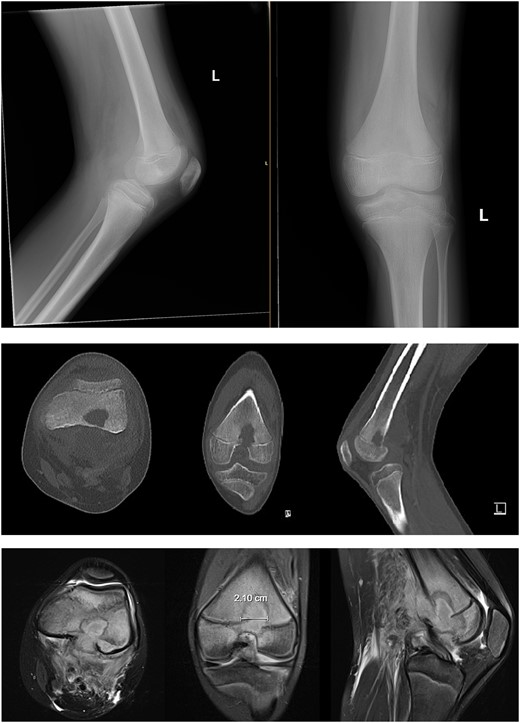

The patient was admitted to the children’s hospital and was started on broad-spectrum intravenous antibiotics. A left knee synovial aspiration was performed, which yielded normal results. A venous ultrasound was performed but was deemed technically unsatisfactory for interpretation. On hospital Day 1, the patient underwent left distal femur irrigation and debridement (I&D) with intraoperative cultures obtained. During the surgical dissection, the popliteal vein was found to be non-compressible, consistent with DVT, prompting the initiation of anticoagulation therapy (rivaroxaban, 15 mg daily) alongside appropriate antibiotic therapy.

Despite initial improvement, the patient’s CRP stabilized at 5.5 μg/ml 6 days post-operatively. Consequently, a repeat I&D with antibiotic bead placement was performed on postoperative Day 7. The patient’s condition improved, with undetectable CRP levels at discharge 14 days after initial hospitalization. Four weeks post-discharge, a repeat venous ultrasound of the affect extremity was performed, demonstrating resolution of the DVT (Fig. 2). In total, the patient received 18 weeks of outpatient oral antibiotic therapy and 9 weeks of anticoagulation therapy. Six months post-hospitalization, the patient was asymptomatic and cleared to return to full activity. After 1-year post-discharge, final radiographs demonstrated no osseous abnormalities, the patient remained asymptomatic, and was released from clinic (Figs 3 and 4).

Ultrasonography obtained in January of 2023 demonstrating resolution of DVT.